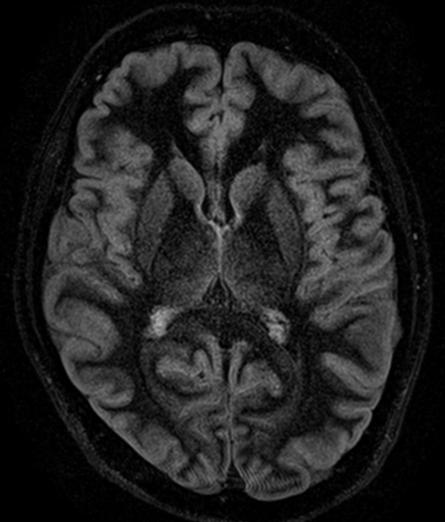

3D FLAIR with DLR. 3D FLAIR Original image. 100s, 0.5x0.5x0.6mm reconstructed

out losing time or signal. The second advantage is the reduction of image acquisition time, as we care less about the signal quality because the noise can be eleminated following the scan,” Prof. Dousset said.

In particular DLR has an important clinical impact in anatomical regions that require a very high resolution, for example parts of the hippocampus and the claustrum.

“The DLR brings a spatial resolution that I have never seen before in neurologic imaging. I recently pointed out a brain area, for example the claustrum, that is almost invisible on standard MRI images even with very high resolution or high field devices. However, thanks

to the DLR we could highlight this kind of brain anatomy. So, indeed, there is a considerable advantage to using this technique.” Prof. Dousset said.

Prof. Tourdias worked at 7T to visualise extremely fine structures of the hippocampus while at Stanford. With DLR, he can now do this task with a 3T. “When we compared the images we realized that by pushing the 3T machine and processing with DLR that we were able to achieve a similar result to what we could achieve with 7T. I think this is the main surprise of the technology.” he said.